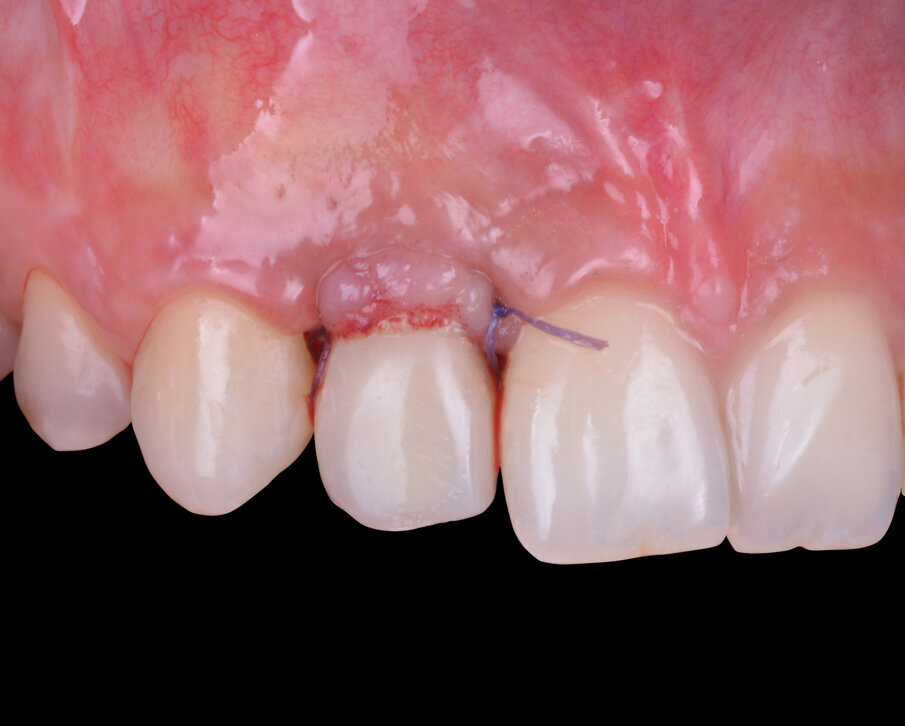

Ad inserimento della fixture avvenuto si rileva la presenza di una piccola fenestrazione vestibolare classificabile come un’atrofia vestibolare di Classe II secondo la classificazione di Chiapasco e Casentini dei difetti ossei perimplantari del 20188 (Fig. 6). La tecnica chirurgica scelta per la gestione del difetto osseo è la GBR. Il primo step contempla di eseguire dei fori di osteopromozione sulla corticale vestibolare attraverso uno strumento rotante a basso numero di giri e senza ausilio di irrigazione con acqua fisiologica così da ottenere un maggior apporto ematico endostale nella regione da trattare e la successiva aggiunta di particolato di osso autologo che conferisca osteoinduttività e osteogeneticità all’innesto (Fig. 7). Il difetto viene gestito impiegando scaffold inorganici, ovvero dei biomateriali che fungono da riempitivi inerti con proprietà osteoconduttive (in grado di guidare la rigenerazione ossea facilitando la stratificazione e l’organizzazione del coagulo su di essi) e di space making (capaci di mantenere lo spazio necessario alla rigenerazione impedendo il collasso parziale o totale dei tessuti molli sovrastanti)9. Nel caso specifico, il biomateriale eterologo innestato è di origine bovina (Nobel Biocare Xenogain 0,2-1 mm); dopo l’accurato posizionamento del biomateriale nella regione da trattare si procede alla protezione dello stesso con una membrana riassorbibile in pericardio bovino con matrice tridimensionale (Ubgen, Shelter/sistema Pericross) stabilizzata per mezzo di pins di fissazione sia palatalmente che vestibolarmente (Fig. 8). L’esecuzione di un’incisione di rilascio periostale del lembo vestibolare permette di ottenere una chiusura per prima intenzione della ferita caratterizzata da una competente interfaccia dei due lembi e da una passivazione degli stessi (Fig. 9). La dimissione della paziente avviene solo dopo aver applicato con cementazione adesiva il Maryland bridge provvisorio prestando particolarmente attenzione a evitare compressioni sui tessuti molli appena trattati chirurgicamente. Durante il periodo di guarigione la paziente viene rivalutata con cadenza mensile per controllare il procedere del fisiologico decorso post-operatorio. A 6 mesi dall’inserimento dell’impianto, dopo opportuni controlli radiografici, si procede con la programmazione della riapertura.

Le valutazioni preliminari evidenziano che in visione occlusale si è ottenuta una restitutio del profilo vestibolare dei tessuti molli e l’architettura della linea muco-gengivale è stata mantenuta tanto da rilevare un’elevata quota di banda cheratinizzata nella regione crestale del processo alveolare (Fig. 10); se non avessimo trovato una situazione clinica come quella descritta, si sarebbe configurata l’indicazione per l’esecuzione di un incremento a fini cosmetici della convessità buccale solitamente gestita con innesti gengivali autologhi o eterologhi. Si procede dunque con la riapertura disegnando un lembo mininvasivo crestale a spessore totale che, in prossimità della vite di copertura, consenta l’accesso per il recupero della stessa e la sua sostituzione con un healing abutment (avvitato a un torque di circa 15 N/cm). I tessuti cheratinizzati (ben rappresentati nell’aerea cervicale perimplantare) vengono stabilizzati grazie a due punti di sutura singoli staccati nella regione mesiale e distale all’impianto stesso. La necessità della paziente di risolvere precocemente i problemi causati da un Maryland bridge poco stabile ed esteticamente non soddisfacente a causa delle modifiche eseguite per salvaguardare le mucose in via di guarigione, rivestono un’indicazione per confezionare una corona in resina acrilica avvitata che viene posizionata il giorno stesso sull’impianto osteointegrato di 12 (Figg. 11, 12).